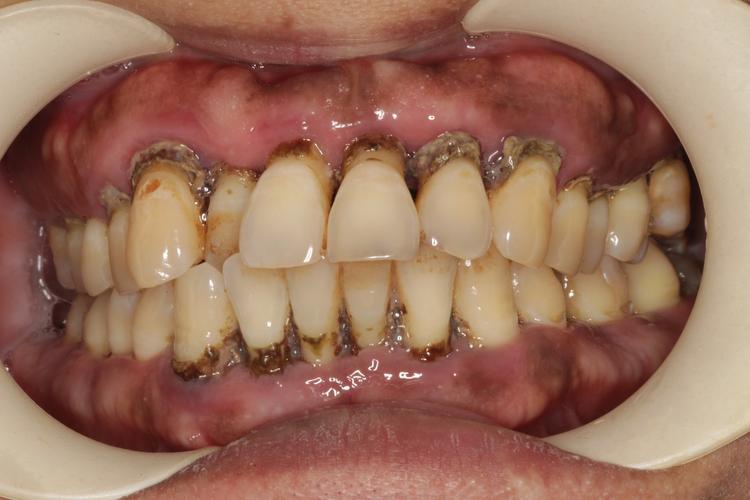

正畸期间牙周炎的临床表现与普通牙周炎既有相似之处,也有其特殊性,早期多表现为牙龈炎症状:刷牙或咬硬物时牙龈出血,牙龈颜色鲜红或暗红,质地松软、光亮,龈缘变厚,龈乳头圆钝,随着病情进展,会出现牙周袋形成,探诊深度超过3mm,探诊时出血甚至溢脓;牙槽骨吸收可通过X线片观察到,表现为牙槽嵴高度降低、骨密度减低;严重时可能出现牙龈退缩、牙根暴露,牙齿松动甚至移位,影响正畸牙移动的稳定性和效果,值得注意的是,正畸患者可能因牙齿移动导致牙龈形态暂时改变,出现“假性牙周袋”,需与真性牙周炎鉴别,这需要专业医生通过临床检查和影像学综合判断。

处理正畸期间的牙周炎,需遵循“先控制炎症,再继续矫正”的原则,多学科协作是关键,急性炎症期(如牙龈广泛出血、牙周袋溢脓、明显疼痛)应暂停正畸加力,优先进行牙周基础治疗:包括龈上洁治(洗牙)清除菌斑和牙石,龈下刮治和根面平整清除牙周袋内的牙结石和感染牙根表面,必要时配合局部药物治疗(如龈下冲洗、上药),对于炎症较重、伴有牙龈增生或牙周脓肿的患者,可能需进行牙周手术(如牙龈切除术、翻瓣术等)彻底清创,待牙周炎症得到控制(牙龈颜色恢复正常、探诊出血明显减少、牙周袋深度变浅)后,再与正畸医生沟通,调整治疗方案,如更换更易清洁的矫治器、减小矫治力、延长复诊间隔等,并在后续治疗中加强牙周维护,治疗过程中需定期监测牙周状况,一般每1-2个月复查一次牙周情况,根据复查结果动态调整正畸力度和牙周治疗措施。